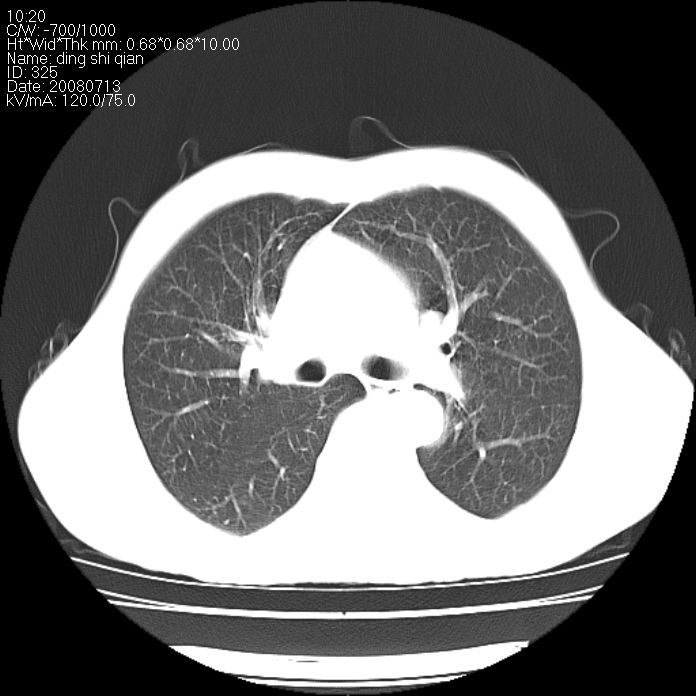

标题: CT14654:男 50岁 近来胸痛 [打印本页]

标题: CT14654:男 50岁 近来胸痛

右侧上肺块状软组织影,浅分叶,边缘毛刺证,与胸膜粘连,考虑:周围性肺癌

右肺上叶周围型肺癌可能性大。

右侧上肺块状软组织影,浅分叶,边缘毛刺证,与胸膜粘连,考虑:周围性肺癌!支持!

首先考虑周围性肺癌,建议强化或穿刺明确